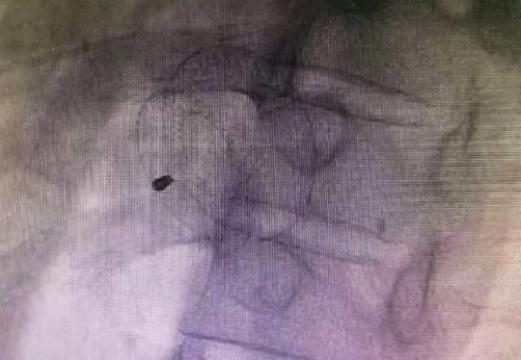

△术中评估

患者刘某,因体检发现存在“先天性心脏病——房间隔缺损”后至宿迁市钟吾医院心血管内科门诊就诊,心脏彩超显示其房间隔缺损约15mm,我院心血管内科主任程春齐接诊患者后,积极与患者及其家属沟通病情,并向他们详细介绍了目前最佳的治疗方案为行“房间隔介入封堵术”。

术前准备完善后,心血管内科团队在介入诊疗中心采用新型国产二代封堵器为患者顺利实施“房间隔介入封堵术”,术后三天患者康复出院。